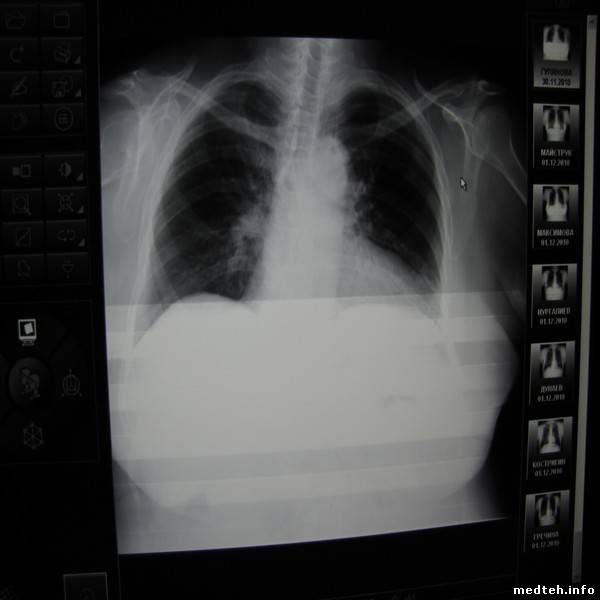

Снимки аппарата и рентгеновские снимки прилагаются.

4918676.jpg (15.6 Kb) · 6837123.jpg (35.3 Kb) · 1013881.jpg (28.9 Kb) · 1075518.jpg (37.0 Kb) · 4876450.jpg (51.3 Kb) · 5301896.jpg (48.8 Kb)